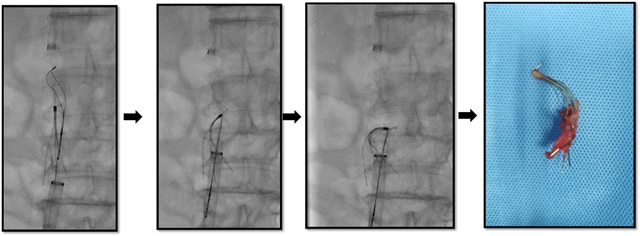

术后取出的下腔静脉滤器及其附着的血管内膜组织

为了避免继续留置滤器可能再次给老人带来血栓形成或其他严重并发症,手术团队决定为老人取出这枚沉睡了6年多的滤器。然而,这枚滤器已经在患者体内留置时间过久,远远超出了其3个月回收的时间窗,手术难度可想而知。

这种远超时间窗取出滤器的病例,文献也少有报道。能否顺利取出滤器着实让手术医生捏一把汗!手术室内,医生先尝试了用常规方法取出滤器失败。接着,胆大心细的介入·血管科医生们改变策略,经过精湛的技术从股静脉成功地揪出了这个“顽固”的家伙!

手术非常顺利,整个操作都是在局麻下完成的,术中老人也并没有出现腹痛不适,术后第二天患者就下床自由活动。术后3天复查显示:下腔静脉及髂静脉未见明显异常,这进一步证实了老人的血栓已被完全清理。老人得知不仅血栓被彻底清理、还取出了这个带了6年多的滤网后,露出了久违的笑容,老人及其家属对手术结果非常满意,也为介入·血管科的老师们竖起了大拇指!